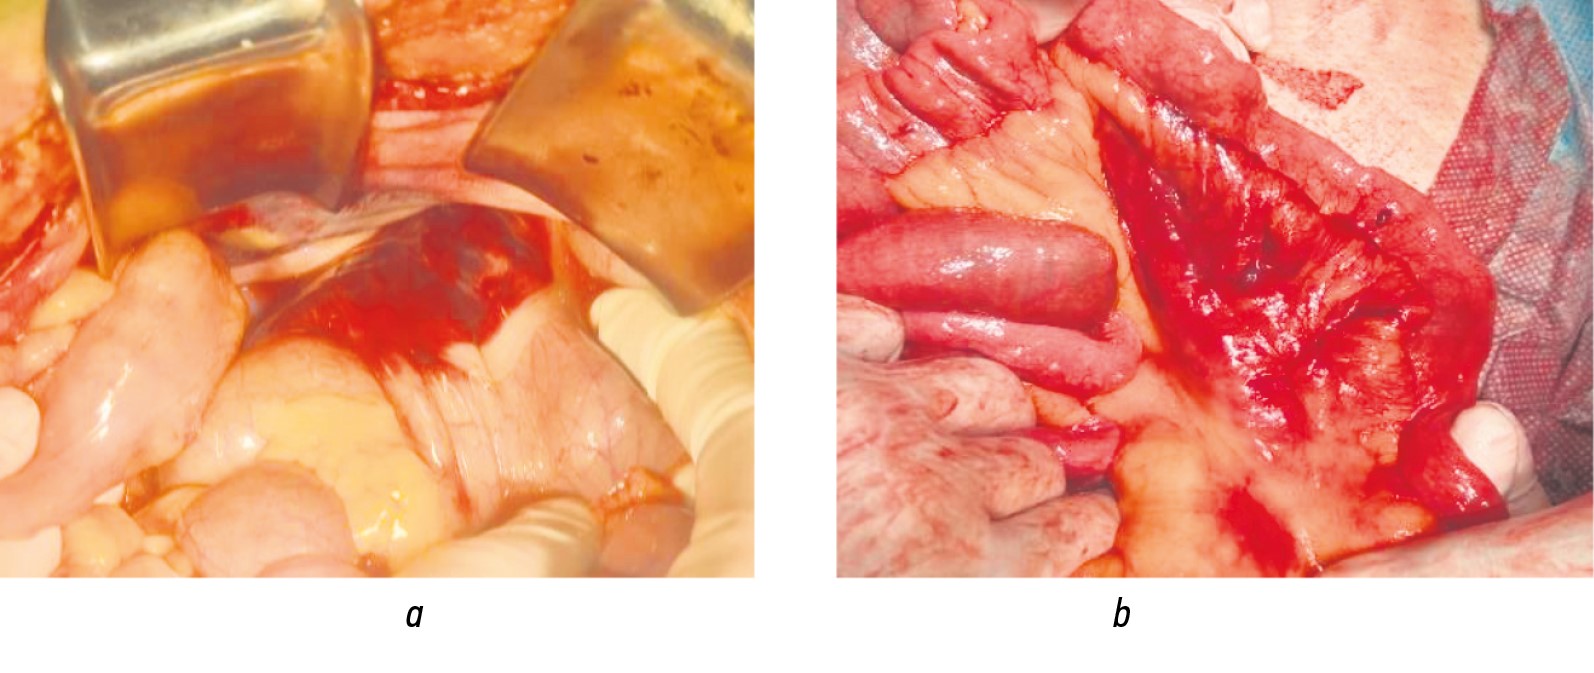

The severe character of multi-organ injuries, combined with pronounced infectious and inflammatory changes in the abdominal cavity, warranted the implementation of an open-abdomen strategy with repeated programmed revisions in 61.5% of MG patients and 56.9% of CG patients. The main indications for its use were the prevention of abdominal compartment syndrome, repeated macroscopic assessment (second look), and control of the infectious focus (source control) (Fig. 6). A specialized peritonitis progression risk scale was applied to refine the latter criterion [14].

Vacuum-assisted or vacuum-instillation laparostomy was used as a temporary abdominal closure technique within the framework of infection source control (Fig. 7).

Fig. 7. Patient, 44 years old. Formation of a vacuum-instillation laparostomy.